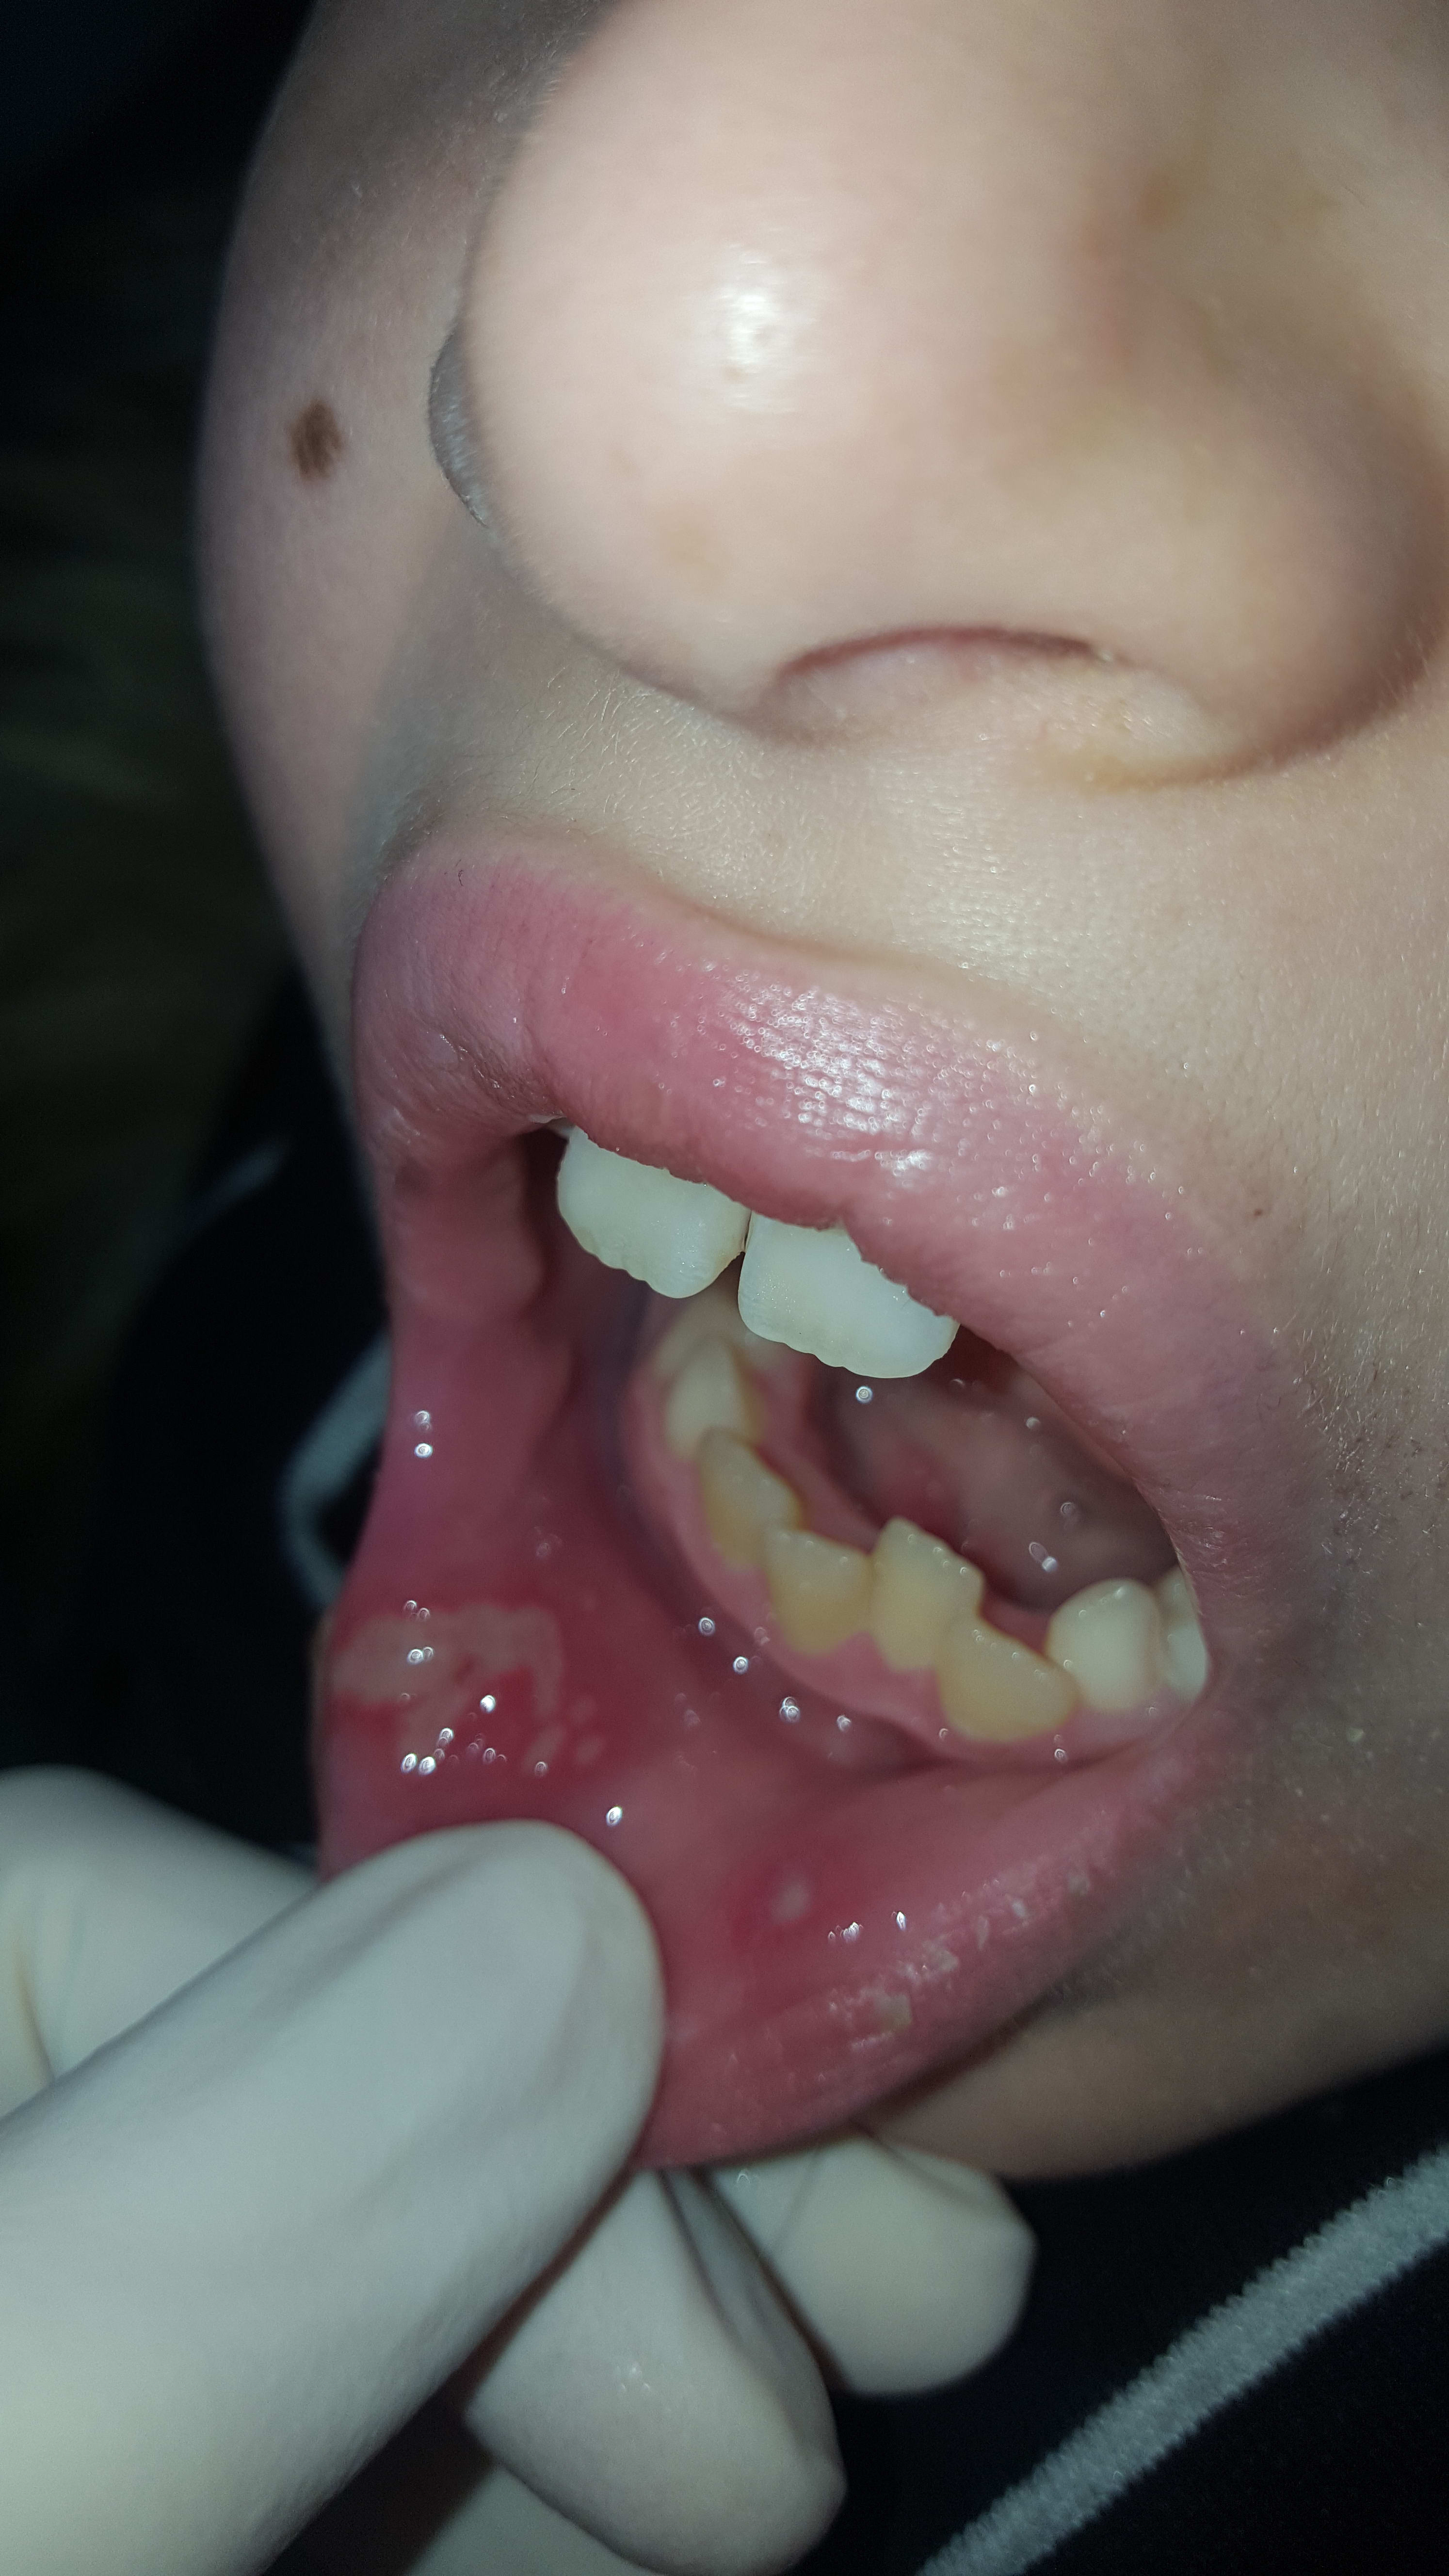

La mère revient en urgence avec son enfant 4 jours plus tard: c'est là que j'ai réalisé les photos ci-jointes. Il y a une importante ulcération labiale droite, la lèvre inférieure est gonflée, douloureuse. Elle serait apparu le lendemain du soin. Elle dit que le soir même il présentait des "points rouges au niveau de la gencive". Elle m'accuse d'avoir provoqué un nouvel aphte lors de la réalisation du soin et veut que je soulage son fils. Globalement perte de confiance envers moi et mes capacités (c'est ce qu'elle a laissé entendre à la secrétaire).

Donc j'en arrive à ma première question: pour vous, lèvre inférieure à droite c'est une morsure ou un aphte? Pour moi c'est plus une morsure. La maman me soutient qu'elle l'a surveillé pour qu'il ne se morde pas mais si il a mangé alors qu'il était encore anesthésié... Il n'a pas d'antécédent médico-chirurgicaux particulier ni de traitement. Est-ce que je devrais chercher une cause systémique si il s'agit d'aphtes multiples? Antécédents d'aphte mais je n'en ai jamais vu plusieurs en bouche en même temps. Je ne pense pas que ce soit une réaction allergique non plus. Pour info j'ai réalisé une para apicale sur 85 à l'articaine 1/200, pas d'anesthésique topique au préalable et j'humidifie mes cotons salivaires avant de les retirer (peu de risque d'abrasion).

clairement, c'est pas un aphte mais une morsure

le gamin se mordille la lèvre pour sentir si çà se réveille...

j'en ai déjà vu des plus impressionnantes...

Hmmm... honnêtement, ça se discute. simple corrélation au premier coup? , puis "récidive" ? Ou traumatisme ? l'apparence multiloculaire permet de discuter l'étiologie traumatique qui ne me semble pas certaine. C'est comment à la palpation ? A la louche, ça m'évoque plus une lésion vésiculeuse ou bulleuse en détersion. je ne peux pas affirmer ce que c'est mais je demanderais un avis médical, c'est sur.